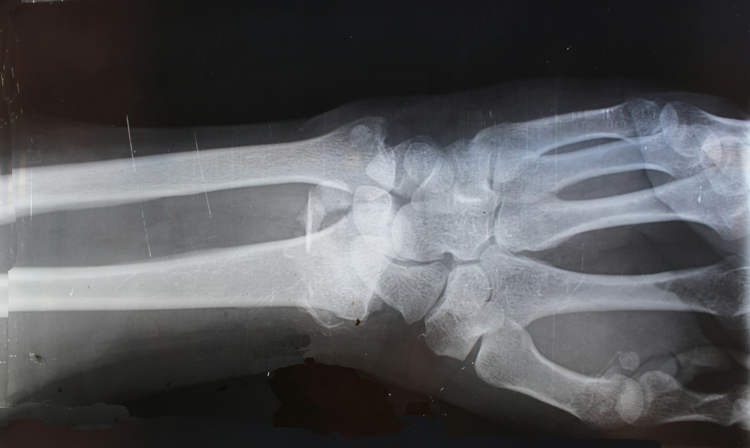

Trường hợp điển hình chữa gãy cổ tay không phẫu thuật phức tạp

Một trường hợp nổi bật khi sử dụng Bone-02 là bệnh nhân bị gãy cổ tay nghiêm trọng nhưng không cần trải qua phẫu thuật truyền thống. Nhờ lớp keo siêu bám dính này, phần cổ tay được cố định chắc chắn, giảm đau nhanh chóng và phục hồi chức năng bình thường chỉ sau vài tuần theo dõi. Đây là minh chứng rõ nét cho hiệu quả vượt trội của Bone-02 đối với những vết thương khó.